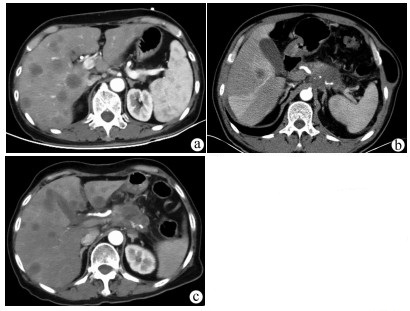

Clinical effect of simultaneous surgical resection of hepatic and pancreatic lesions versus systemic chemotherapy in treatment of resectable pancreatic cancer with liver metastasis

2022, 38(3): 622-628. DOI: 10.3969/j.issn.1001-5256.2022.03.023

Abstract(1500) HTML (1256) PDF (2734KB)(76)

Abstract:

Objective  To investigate the clinical effect of simultaneous surgical resection of hepatic and pancreatic lesions versus systemic chemotherapy in treatment of resectable pancreatic cancer with liver metastasis (PCLM).  Methods  A retrospective analysis was performed for related data of the patients with PCLM who were admitted to Shengjing Hospital of China Medical University from January 2013 to May 2020, and the patients with resectable PCLM were screened out and then divided into surgery group and chemotherapy group. The propensity score matching (PSM) method was used to reduce the impact of data bias and confounding factors. The independent samples t-test or the Mann- Whitney U test was used for comparison of continuous data between two groups, and the chi-square test was used for comparison of categorical data between two groups. The Kaplan-Meier method was used to calculate survival time, and the log-rank test was used for evaluation. The univariate and multivariate Cox regression models were used to investigate the independent risk factors for survival.  Results  A total of 56 patients with resectable PCLM were screened out, with 33 patients in the surgery group and 23 patients in the chemotherapy group, and there were 15 patients in each group after PSM. The surgery group had a significantly shorter median overall survival time than the chemotherapy group before PSM (6.6 months vs 10.4 months, χ2=4.476, P=0.034) and after PSM (6.4 months vs 10.5 months, χ2=4.309, P=0.038). The multivariate Cox regression analysis showed that poorly differentiated tumor (hazard ratio [HR]=4.945, 95% confidence interval [CI]: 1.980-12.348, P=0.001) and absence of postoperative chemotherapy (HR=3.670, 95%CI: 1.437-9.376, P=0.007) were independent risk factors for poor prognosis in patients with PCLM.  Conclusion  Compared with chemotherapy, simultaneous surgical resection of hepatic and pancreatic lesions fails to prolong the overall survival time of patients with resectable PCLM. Patients with poorly differentiated tumor and those without postoperative chemotherapy tend to have poor prognosis.